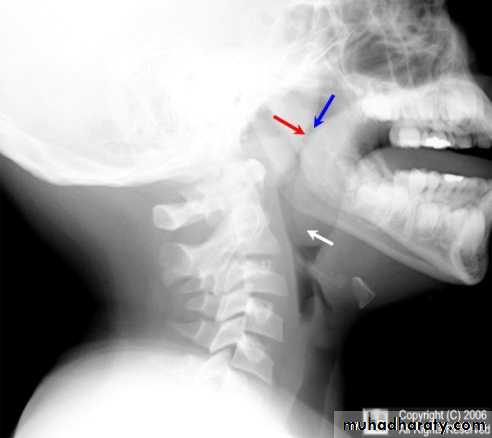

X-ray of the postnasal space